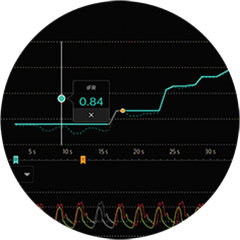

Solo iFR

tiene datos de resultados de pacientes validado clínicamente en los estudios de fisiología más grandes jamás realizados. Ningún otro índice de reposo tiene datos de resultados de pacientes que respalden su uso.